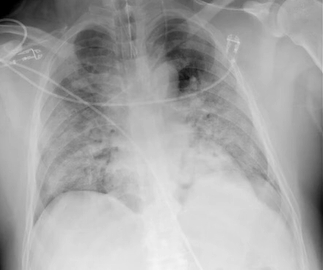

• 호흡기 감염 → 폐렴, 기관지염, 폐농양 (가장 흔한 원인)